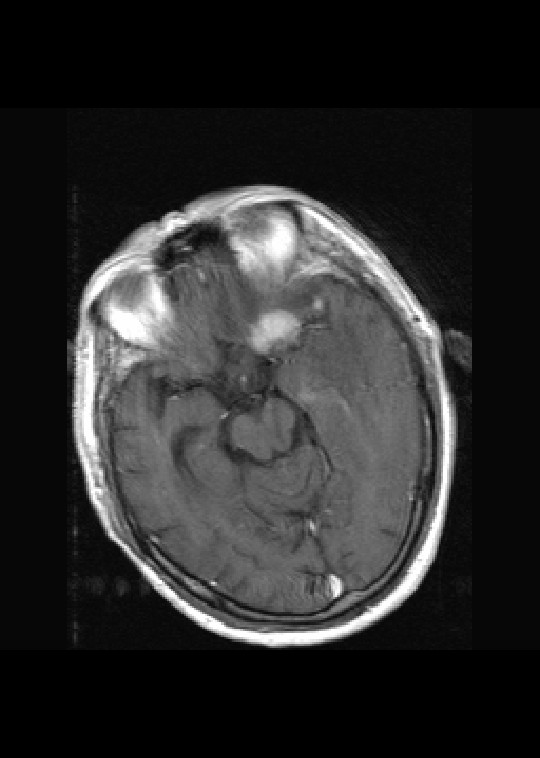

标题: MRI2527:脑部肿瘤,(病理结果:淋巴瘤)

(左额颞叶)非霍奇金淋巴瘤,b细胞性,弥漫性大b细胞型。免疫组化结果:cd45(lca) +,vimentin +,ck(ae1/ae3) -,ema -,cd3 -,cd20 +++,cd30 -,plap -,cd79a +,gfap -,alk -,s-100 -。

左侧基底节区病灶t1wi呈不均匀稍低信号,t2wi呈稍高信号,周围伴有水肿。增强扫描呈均匀团块样或者抱拳样明显强化,相邻的柔脑膜亦见线样强化。首先考虑淋巴瘤。可惜没有ct平扫,如果ct平扫病灶呈高密度,那么更支持pcnsl的诊断。

病理结果:(左额颞叶)非霍奇金淋巴瘤,b细胞性,弥漫性大b细胞型。免疫组化结果:cd45(lca) +,vimentin +,ck(ae1/ae3) -,ema -,cd3 -,cd20 +++,cd30 -,plap -,cd79a +,gfap -,alk -,s-100 -。

左侧基底节区病灶t1wi呈不均匀稍低信号,t2wi呈稍高信号,周围伴有水肿。增强扫描呈均匀团块样或者抱拳样明显强化,首先考虑淋巴瘤。